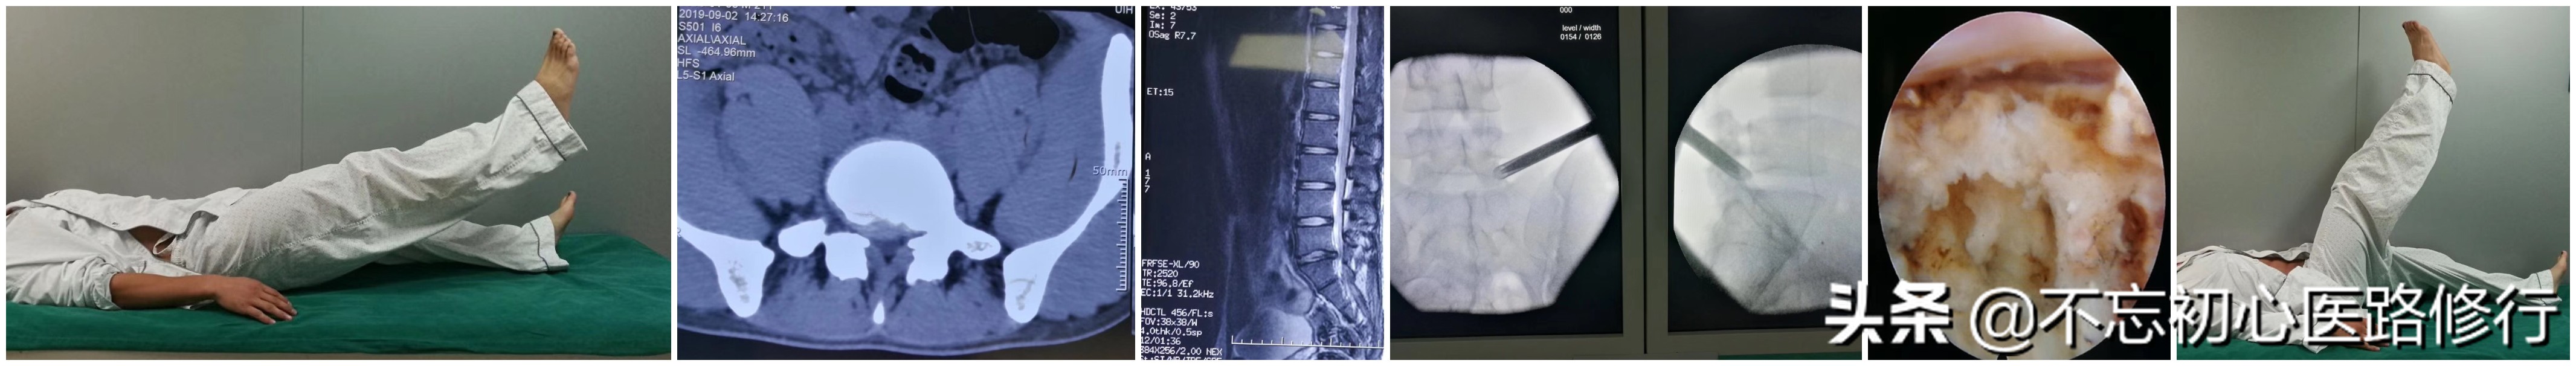

1)直腿抬高试验:病人仰卧,伸膝,被动抬高患肢,抬高在60°以内出现头痛为阳性。因为正常的神经根能滑动4mm,当受压或者粘连时出现疼痛。

2) 直腿抬高加强试验:在直腿抬高阳性的时候,适当减低高度,待放射痛消失,再被动背屈踝关节以牵拉坐骨神经,如再次出现坐骨神经痛,则为阳性。

实线是直腿抬高试验,虚线是加强实验

1)直腿抬高法:患者平卧于平板床上,腿伸直,下肢自主抬高,直至极限则停止。15次为1组,每日10 组。

2)单侧屈腿交替蹬直法: 患者平卧于平板床上, 一侧屈髋、屈膝各90°,小腿与床面平行,踝关节保持 背伸,用力将下肢向身体远端蹬直,缓慢放平下肢,左右交替。25次为1组,每日10组,分次训练。

3)侧卧抬腿法:侧卧位,保持躯干与下肢在同一条体侧线上,侧方抬高下肢。每次 10min,每日 3 次。